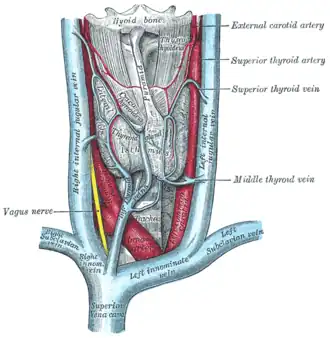

The thyroid gland and its relations

The thyroid gland and its relations -

The right and left vagus nerves descend from the cranial vault through the jugular foramina,[5] penetrating the carotid sheath between the internal and external carotid arteries, then passing posterolateral to the common carotid artery. The cell bodies of visceral afferent fibers of the vagus nerve are located bilaterally in the inferior ganglion of the vagus nerve (nodose ganglia).The vagus runs parallel to the common carotid artery and internal jugular vein inside the carotid sheath.

Right Vagus Nerve: The right vagus nerve gives rise to the right recurrent laryngeal nerve, which hooks around the right subclavian artery and ascends into the neck between the trachea and esophagus. The right vagus then crosses anterior to the right subclavian artery, runs posterior to the superior vena cava, descends posterior to the right main bronchus, and contributes to cardiac, pulmonary, and esophageal plexuses. It forms the posterior vagal trunk at the lower part of the esophagus and passes through the diaphragm to enter the abdomen through the esophageal hiatus.

Left Vagus Nerve: The left vagus nerve enters the thorax between left common carotid artery and left subclavian artery and descends on the aortic arch. It gives rise to the left recurrent laryngeal nerve, which hooks around the aortic arch to the left of the ligamentum arteriosum and ascends between the trachea and esophagus. The left vagus further gives off thoracic cardiac branches, breaks up into the pulmonary plexus, continues into the esophageal plexus, and enters the abdomen as the anterior vagal trunk by way of the esophageal hiatus of the diaphragm.